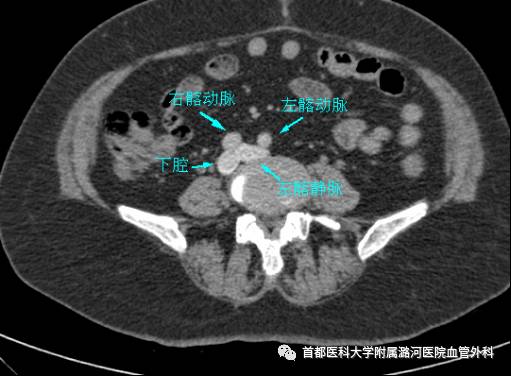

下肢CTV

下肢静脉CTV:

3D打印模型

下腹部平扫也能初步判断有没有左髂静脉压迫,对于怀疑该疾病的可以常规检查下腹平扫CT。